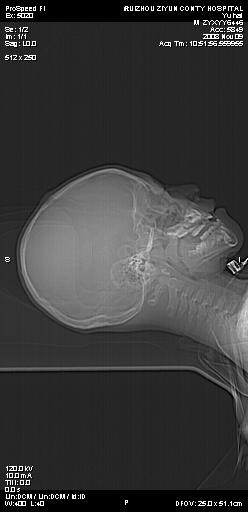

标题: PED1637:M 6Y 顶部无痛性包块两月。 [打印本页]

标题: PED1637:M 6Y 顶部无痛性包块两月。

2、颅骨局部缺失,边缘光滑、整齐

颅骨的病损表现为内外颅骨板层不规则的锋利的破坏,形成“斜边缘”,有一定的特点

颅骨为好发部位,生长缓慢,常位于顶骨、枕骨及颞骨,表现为颅骨缺损,呈圆形或椭圆形,边界清,无硬化

事发冠状缝与矢状缝交界区,密度较低,考虑表皮样囊肿可能性大,其次不除外嗜酸性肉芽肿